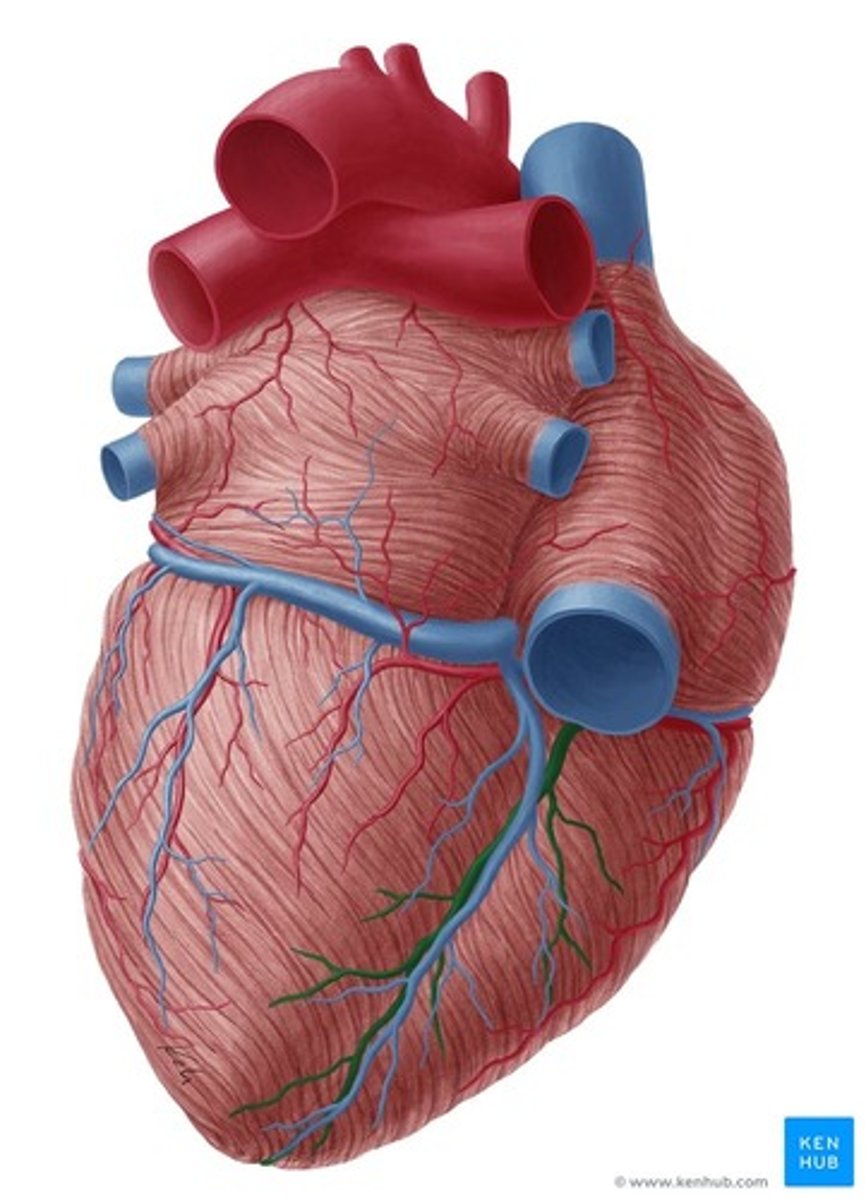

bruzda wieńcowa

coronary sulcus

Jak biegnie bruzda wieńcowa?

w płaszczyźnie prostopadłej do osi serca

bruzda międzykomorowa przednia

anterior interventricular sulcus

bruzda międzykomorowa tylna

posterior interventricular sulcus

Jak biegną bruzdy międzykomorowe?

od bruzdy wieńcowej w kierunku koniuszka serca

Co tworzą bruzdy międzykomorowe w okolicy koniuszka serca?

wcięcie koniuszka serca

wcięcie koniuszka serca

notch of cardiac apex